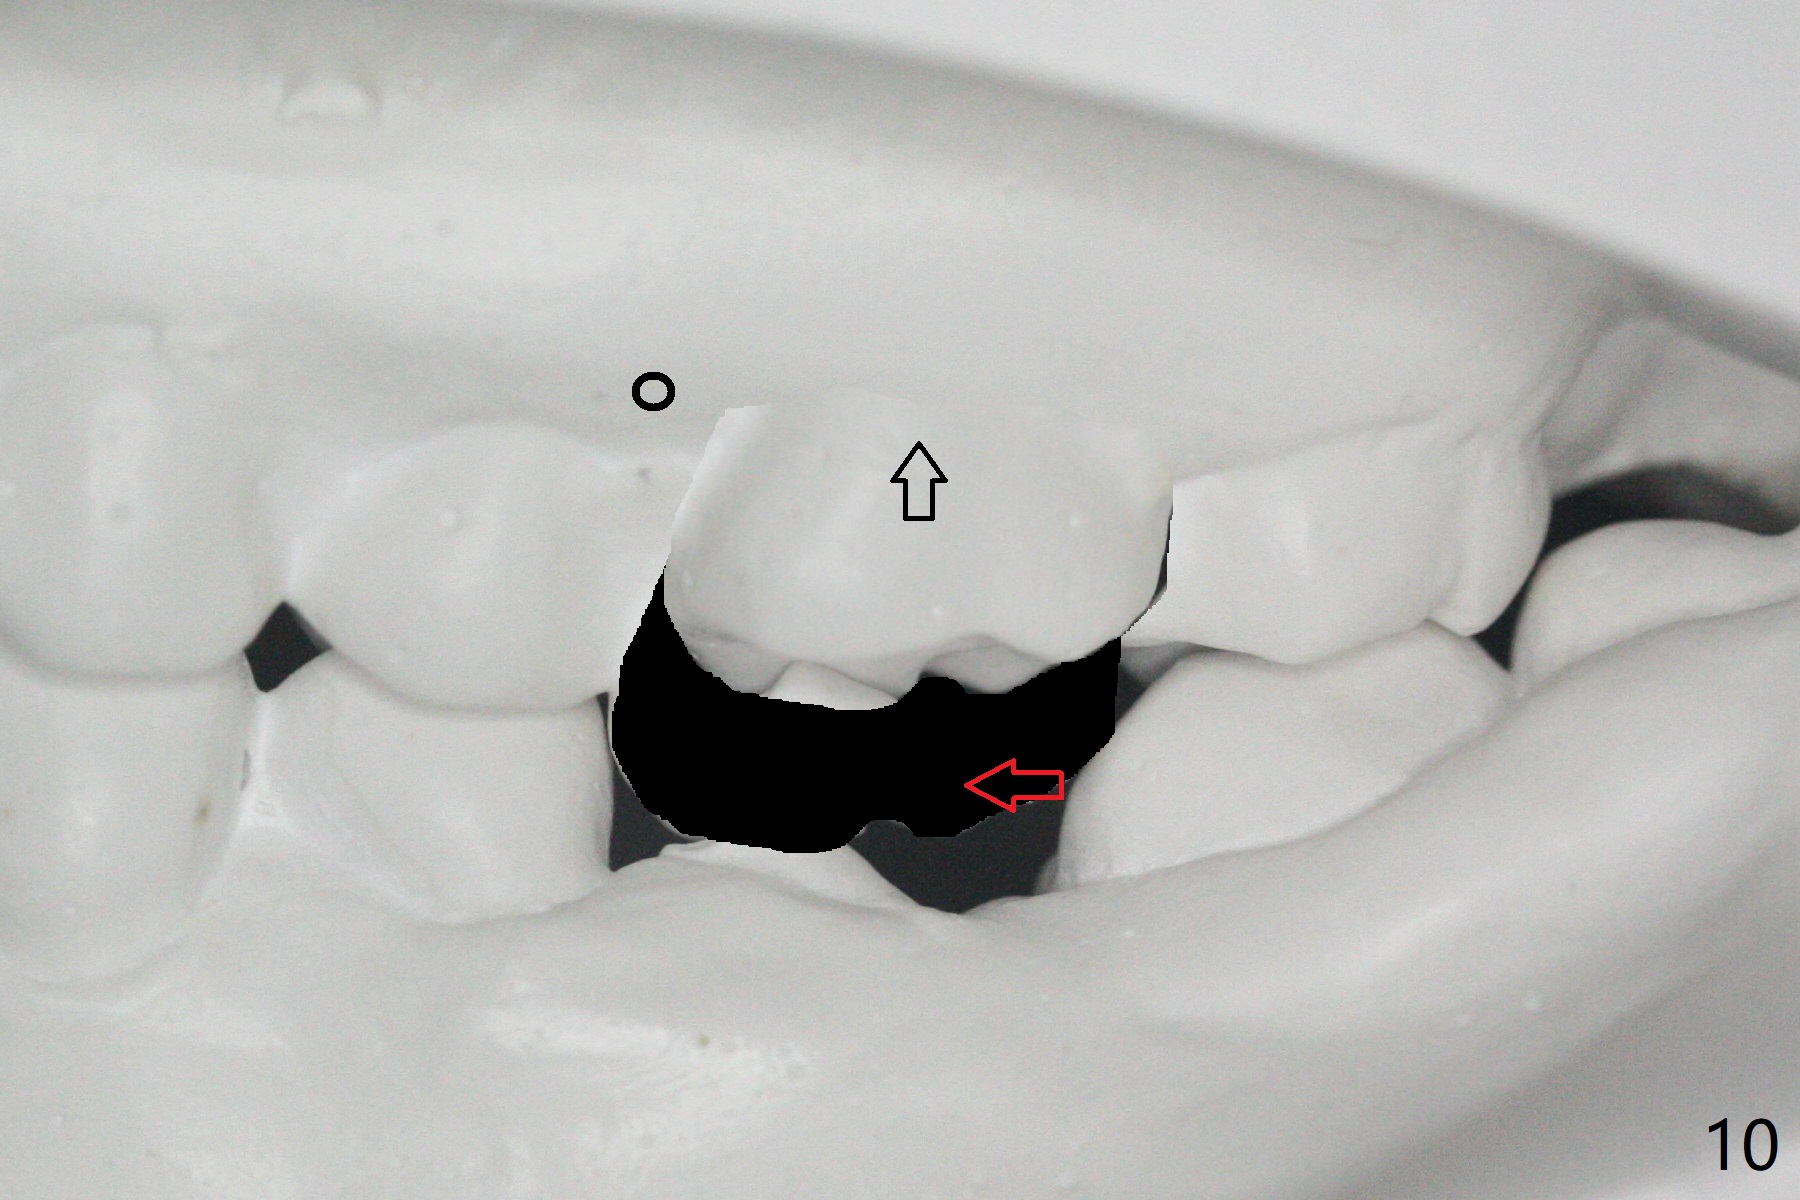

初步计划:第一期安置矫正器,排列,建立正常前牙覆合覆盖,二类牵拉。尽量竖直左下7,8(图十一:白色轮廓);使用两个微型植体(图九:黑线(两个植体之间放置power chain(红线)))压入左上6(图十(圆圈:近中微型植体),与图三对比),为左下7近中移位(红色箭头)创造空间。

第二期在左下4和5之间植入微型植体作为支抗(图十一:红色),利用7远中长勾(粉红色)和橡皮筋,先让7平行近中移位,控制根torque。A 31-year-old woman with Class II Division I malocclusion requests orthodontic treatment without extraction of LL8. U8s and LL6 have been extracted with SRP. The 1st stage will be alignment , intrusion of UL6, upright of LL7 and 8 and correction of Class II malocclusion using double twin.